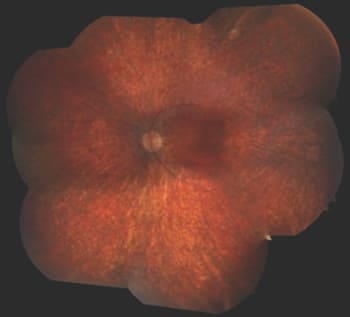

Patient 3 has high hyperopia (+8.00 OU), nystagmus, VA of only LP and a normal-appearing fundus. She was diagnosed at the age of six months because of poor responses to visual stimuli, photophobia and undetectable responses on ERG testing. Fundus photos at 25 years of age are shown in Figure 6, and autofluorescence images are shown in Figure 7.

Figure 6. Fundus photographs of a 25-year-old patient with mutations in GUCY2D show normal optic discs, mild attenuation of the arterioles and normal maculas. There is some minor RPE mottling in the far periphery.

Patient 3 has LCA due to mutations in the GUCY2D (guanylate cyclase) gene. GUCY2D is one of the key enzymes within the phototransduction cascade. Mutations in this gene prohibit reopening of cyclic guanosine mono-phosphate (cGMP)–gated cation channels after photoexcitation, thereby maintaining a state resembling continuous light exposure. Patients with mutations in this gene typically have VA in the LP range, with a few reports of VA up to 20/40.9 In most cases, the fundus remains normal throughout life, although granular pigmentary changes may sometimes develop in the periphery.

Recent studies have shown that macular SD-OCTs in most patients with LCA due to mutations in GUCY2D are relatively normal.9 Adeno-associated vector-based gene replacement therapy studies in knockout mouse models show promise as a future therapeutic intervention.10 Because the VA is typically in the range of LP from birth and appears static, there is a limited time frame during which gene therapy may be administered in these patients in order to retain some visual function.